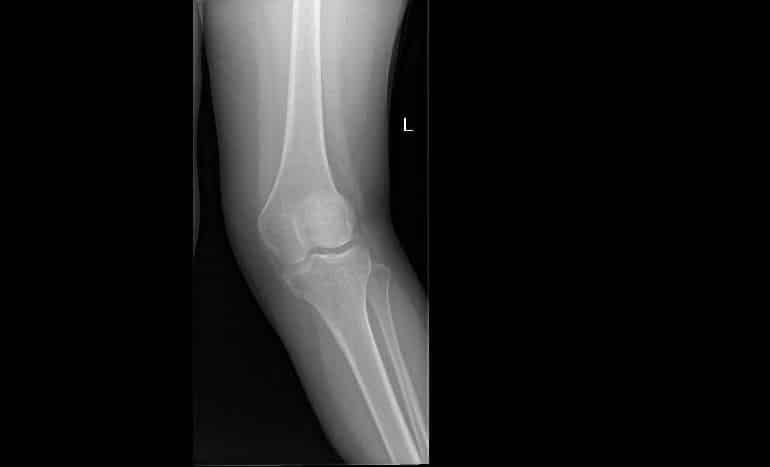

أسهم بفضل الله فريق طبي في قسم جراحة العظام والتخدير والعمليات بمستشفى الملك خالد ومركز الأمير سلطان للخدمات الصحية بالخرج في إنهاء معاناة فتاة من تشوه في الركبة اليسرى واعوجاج خارجي (ركبة فحجاء) وعرج بالمشي.

وقرر الفريق المعالج بعد عمل الأشعة المطلوبة والفحوصات اللازمة ووضع خطة علاجية إجراء عملية باستخدام تخدير نخاعي (نصفي) وتم إصلاح اعوجاج عظمة الفخذ وعظمة الساق والتشوه بالركبة اليسرى، وبفضل من الله تكللت العملية بالنجاح ، حيث تعتبر هذه العملية من العمليات التخصصية المتقدمة في جراحة العظام.